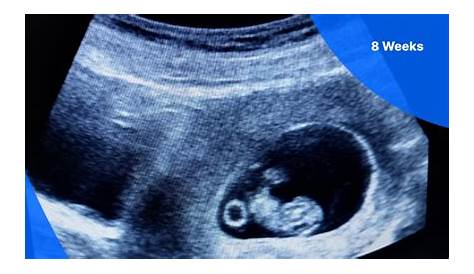

Сегодня я прошла ультразвуковое исследование, и доктор сказал, что мой гестационный мешок измерялся 8 недель, но ребенок измерялся только 6 недель/2. Мне 8 недель в соответствии с последним периодом, 28-дневным циклом! Вчера я провела 8-недельное сканирование, и техник сказал, что ребенок измеряется в 6 недель 4 дня и сердцебиение не обнаружено.

Но ультразвук показал, что ребенку всего 6 недель. У меня также есть субхоральное кровотечение, поэтому я подумал, что мне 8 недель, пошел на ультразвук и измерялся в 6 недель. Все еще слишком мал, чтобы увидеть сердцебиение.

Технология не нашла сердцебиение ребенка и мешок, измеренные в 6 недель, хотя … сегодня я точно 7 недель. На сканировании они могли видеть гестационный мешок, желточный мешок и ребенка (полюс плода) и все было в нужном месте, однако они сказали нам, что ребенок только измерял. Я думал, что я был 7 недель, но ребенок измерял 6 недель, и она смогла найти мешок и желток и все, но не было никакого фетального полюса или сердцебиения.

Ультразвук измеряет ребенка на 6 неделе, но сердцебиение не может быть обнаружено.

Я сразу понял, когда увидел эмбрион на мониторе, что он выглядел слишком маленьким в течение 8 недель. Врач посоветовал мне измерять 6 недель, и сердцебиение было на низком уровне 99 вечера. Ультразвуковая техника смогла найти ребенка.